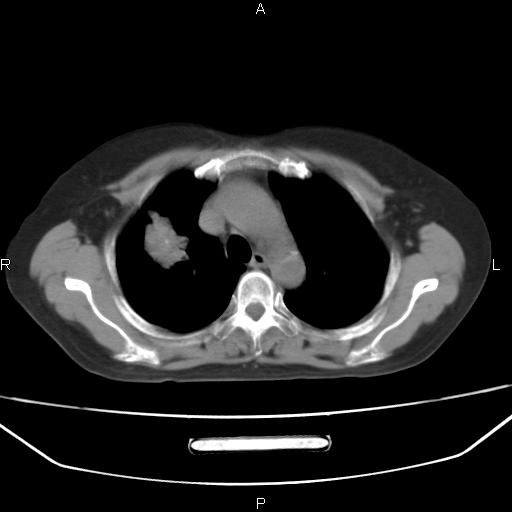

患者,女,66岁。健康体检胸部透视发现右上肺片状阴影。既往无不适,患者自诉三个月前曾有低热病史体温37.5左右一周。用药后缓解。至今无其它不适。请老师们指导指导。

考虑:右肺上叶周围型肺癌(分叶状肿块+砂粒状钙化+胸膜尾征)。

病灶见明显分叶、大小较大(大于3cm?),老年人,多考虑:肺癌,建议穿刺活检。

典型的中心型肺癌,尖段支气管阻塞。

以下是引用dyqct在2010-6-3 9:32:00的发言:[br]考虑:右肺上叶周围型肺癌(分叶状肿块+砂粒状钙化+胸膜尾征)。

不像中央型啊

周围性肺癌,

右肺上叶周围型肺癌可能性大。

考虑:右肺上叶周围型肺癌